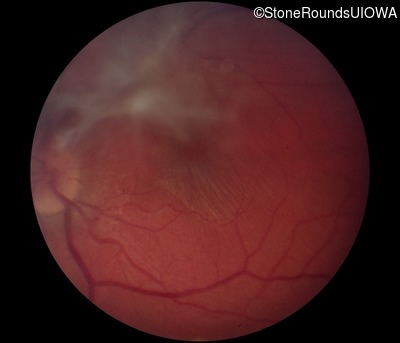

Fundus Photography - Right - 20/125 -2 sc

Exemplar